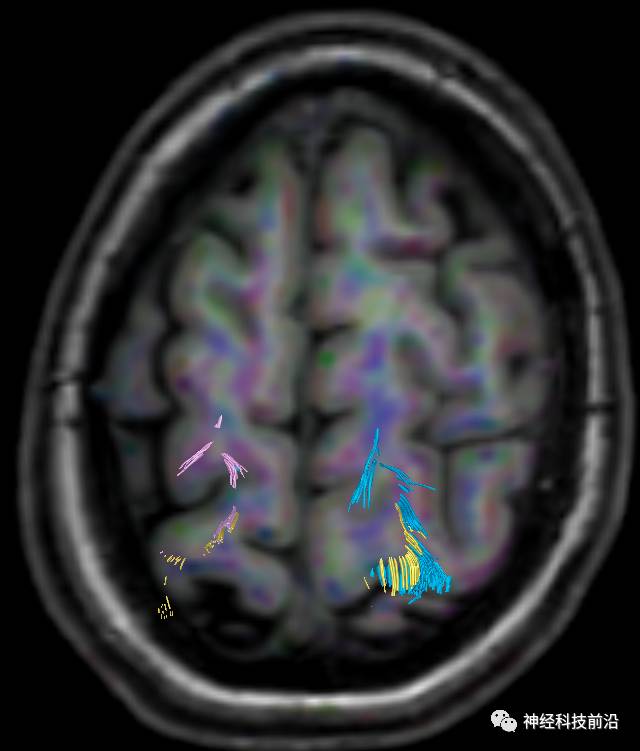

DTI原始图像

DTI原始图像与T1融合图像